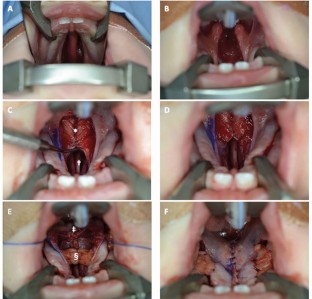

Kriens O B. An anatomical approach to veloplasty. Plast Reconstr Surg 1969; 43: 29-41.

Sommerlad B C. A technique for cleft palate repair. Plast Reconstr Surg 2003; 112: 1542-1548.

Furlow L T Jr. Cleft palate repair by double opposing Z-plasty. Plast Reconstr Surg 1986; 78: 724-738.

Furlow L T. Cleft palate repair by double opposing z-plasty. Oper Tech Plast Reconstr Surg 1995; 2: 223-232.